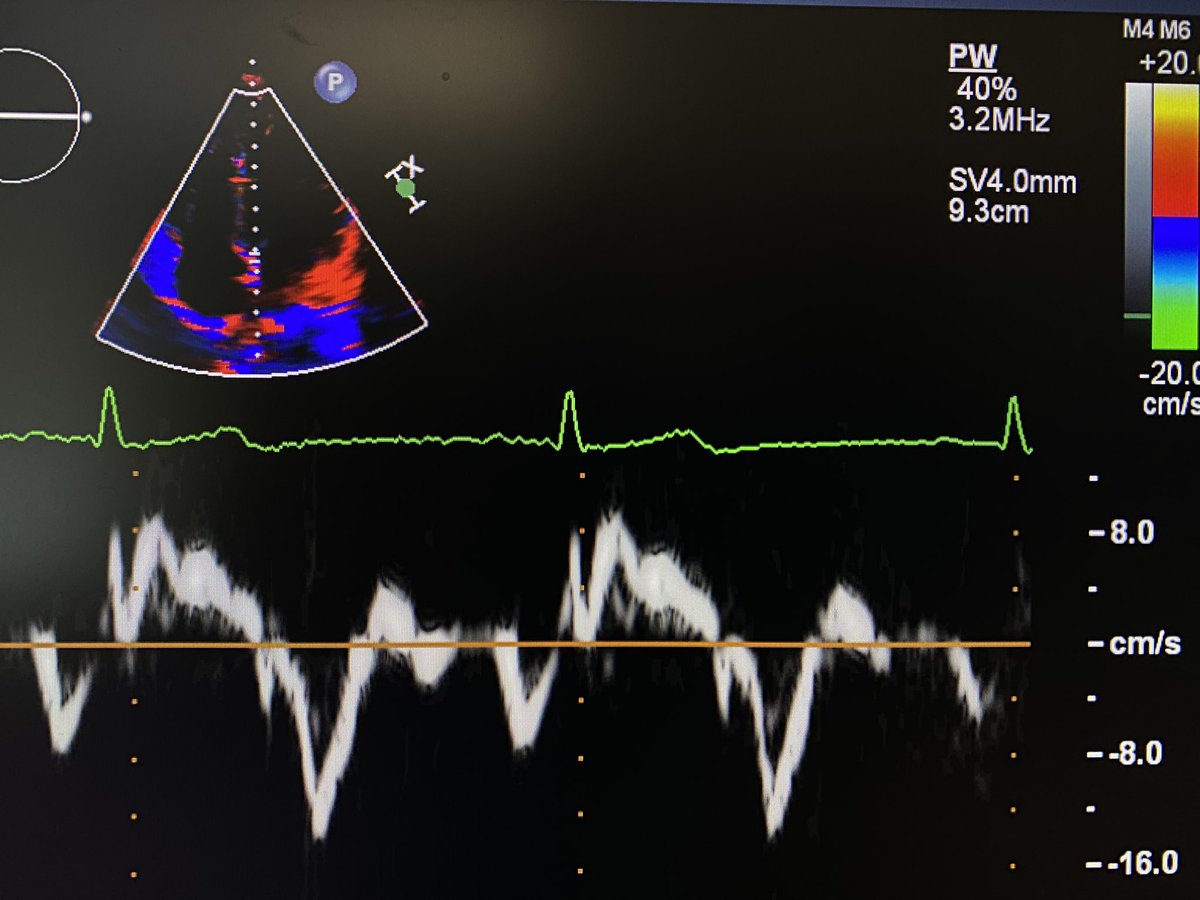

Elmore, Ahern, @BMLevitan, Satin et al. @universityofky shed light on RRAD, a protein that helps regulate calcium channels in the heart. They find its tail region is crucial for both attaching to the cell membrane and influencing heart function. hubs.la/Q02Gm3H60